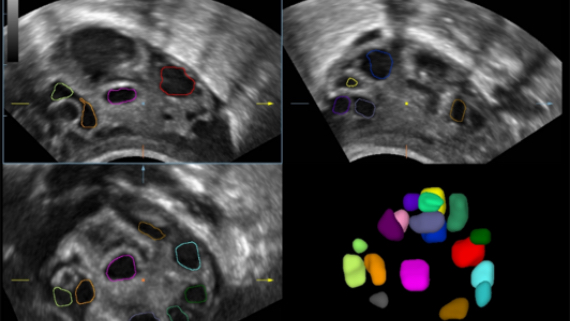

DE11-3E ?ift Hacimli ??zĂŒm

DE11-3E ?ift Hacimli ??zĂŒm

Klinik G?rĂŒntĂŒler